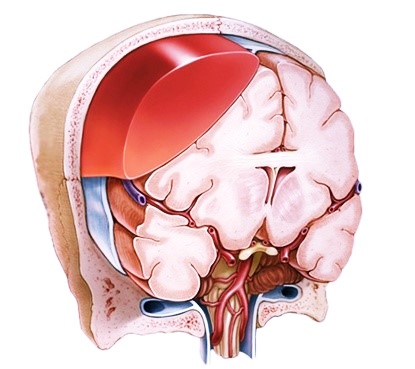

Формирование субдуральной гематомы наблюдается после разрыва интракраниальных вен, которые проходят в субдуральной области, в результате получения черепно-мозговой травмы. В редких случаях гематома возникает по причине нетравматической церебральной сосудистой патологии, из-за проблем со свертываемостью крови, при лечении антикоагулянтами. Есть вероятность двустороннего формирования субдурального кровоизлияния, что отличает его от эпидуральной гематомы.

Скопление крови в головном мозге В результате кровь может скапливаться между черепом и внешней мозговой оболочкой. Такое скопление крови называется эпидуральной гематомой. В других случаях кровь скапливается между тканями внешней и средней мозговой оболочки. Такое скопление крови называется субдуральной гематомой.